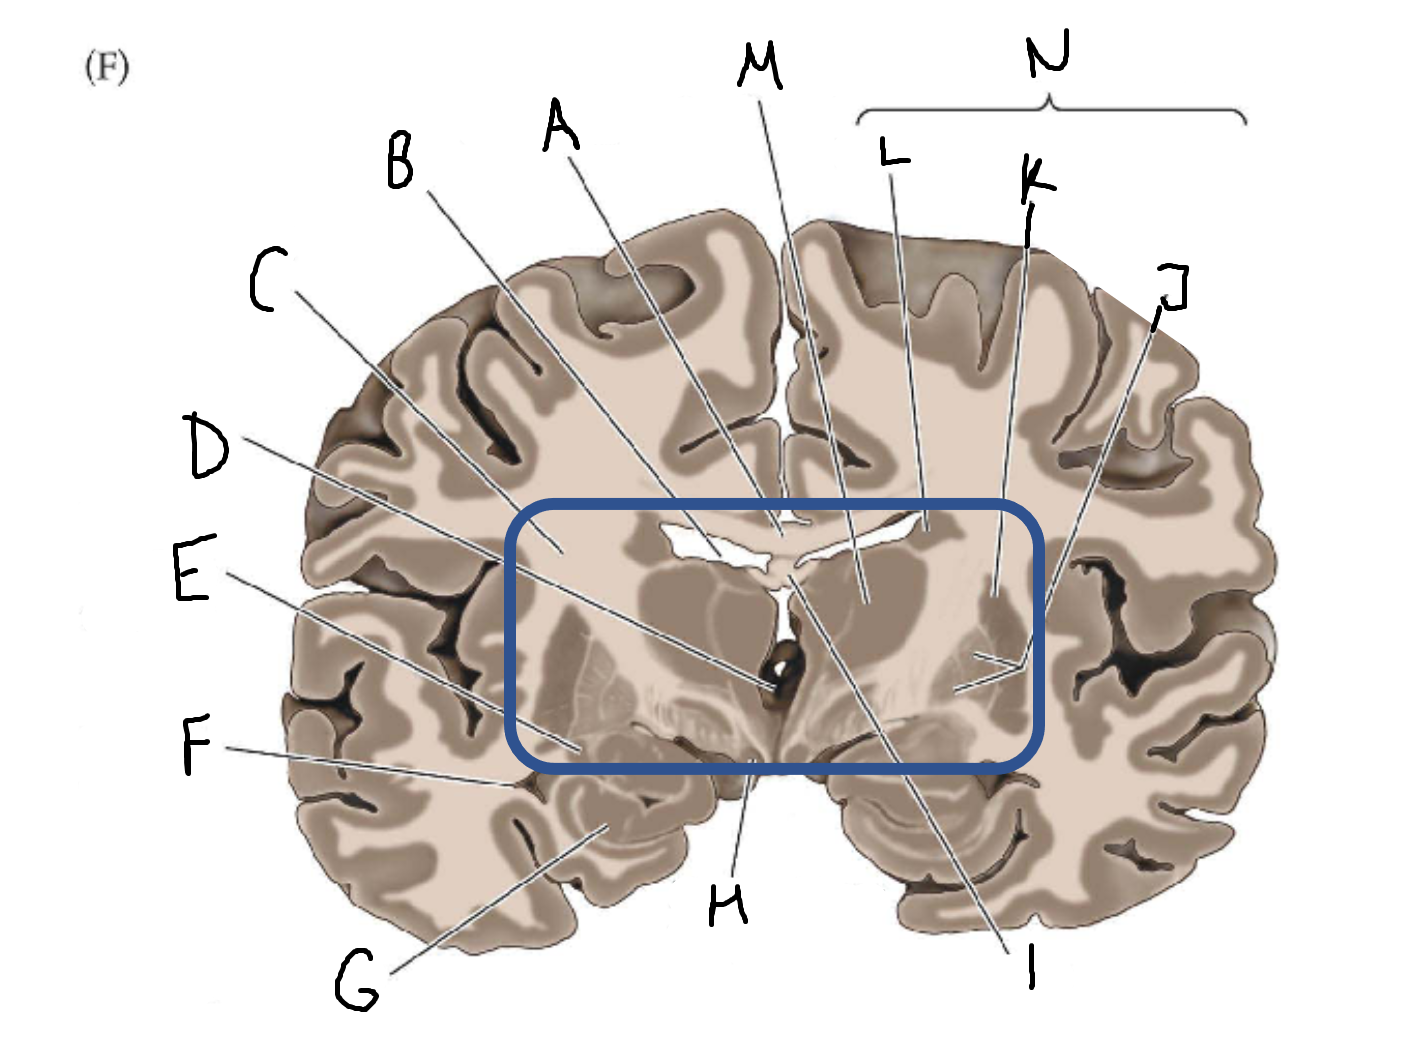

A

corpus callosum

B

lateral ventricle

C

internal capsule

D

third ventricle

E

tail of caudate nucleus

F

lateral ventricle

G

hippocampus

H

mammillary body

I

fornix

J

globus pallidus

K

putamen

L

caudate

M

thalamus

N

basal ganglia